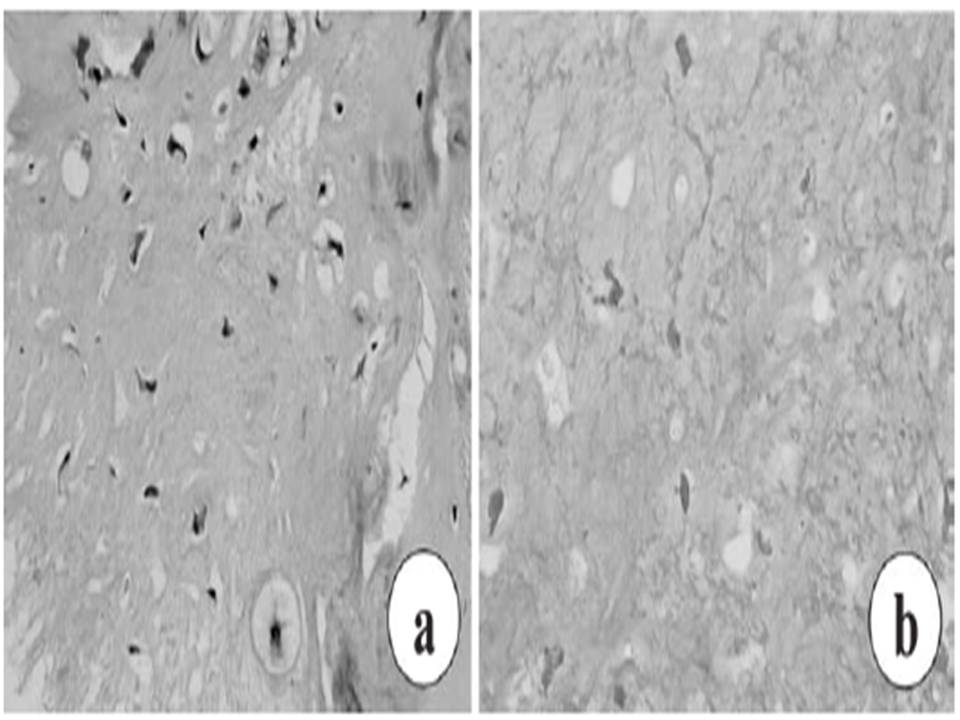

Biopsy specimen. a) Cells varying in size and shape with nuclear atypia and multivesicular vacuolation of cytoplasm. b) Two weeks after electrochemotherapy, histological analysis of core needle biopsies revealed 90% tumor cell necrosis

H&E x 200 |